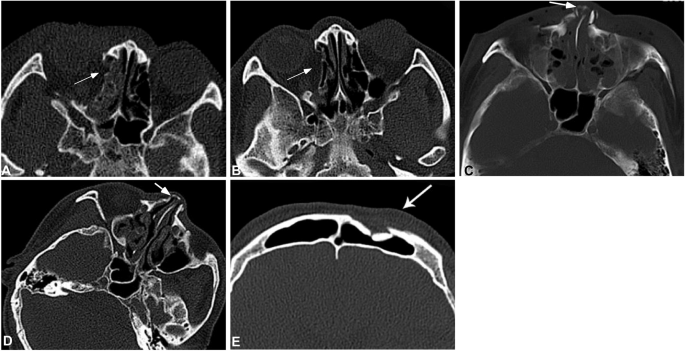

Among all the patients, 356 had bone fractures involving the orbital wall, including 134 involving the medial orbital wall, 121 external orbital wall, 67 orbital floor, 12 superior orbital wall and 22 optic canal wall. In analysis of 126 CT scans of 40 patients with medial orbital wall fractures, soft tissue swelling existed within one week of injury in all patients, and seven patients (17.5%) had swelling of the internus. At the early stage of injury, the bone fracture line of the medial orbital wall was clear and sharp, and during two to three weeks following injury, smooth depression appeared at the original fracture site with some patients having adipose tissue and intraorbital muscle at the depression. During the study period, a significant difference (P < 0.05) existed in the signs studied except for thickness of the medial rectal muscle (Table 3 and Fig. 2A,B)

Facial fractures at different sites. A&B. A male patient aged 52 years had a traffic accident with fractures on the right orbital wall and bilateral ribs. On the day of injury, right orbital wall fracture was demonstrated with clear and sharp fracture lines, effusion in the adjacent ethmoid sinus (arrow) and soft tissue swelling (A). One month later (B), the original fracture site was smooth and depressed (arrow) with no swelling in the soft tissues. (C) A male patient aged 21 years was injured in the nose with nasal deformation. Computed tomographic scanning demonstrated clear a fracture line (arrow) in the nasal bone, with swelling in the adjacent soft tissues and effusion in the ethmoid sinus. (D) Computed tomography one month later, the fracture line became blunt with disappearance of the soft tissue swelling and effusion in the ethmoid sinus. However, the mucous membrane of the ethmoid sinus was still thickened. (E) A male patient aged 51 years had violent assault. Computed tomographic scanning showed old fracture lines at the left frontal sinus wall with clear fracture lines and absorption at the edge of the fracture lines (arrow).

Fifty patients had nasal fractures which were caused by high-energy impact, including traffic accidents in 23 cases, violent assault in 13 and other reasons in 14. Nineteen patients (38%) had concurrent nasal septum fractures and 12 (24%) had concurrent fractures of the frontal process of the maxilla. At the early stage, all fractures had swelling in adjacent soft tissues. The swelling gradually disappeared one week later, the fracture line became blunt three weeks later but could still be seen over two months with different degrees of bone absorption at the fracture line. A significant (P < 0.05) difference existed in the sharpness and bluntness of the fracture line (Table 4 and Fig. 2C).

The key to differentiating new and old bone fractures lies in injury mechanism, sharpness or bluntness of fracture lines and soft tissue injury. One patient who had had old frontal bone fractures was injured once again, with bruise and hemorrhage at the injured frontal area, but he denied having been injured with frontal fractures. CT images showed blunt and sclerotic fracture lines immediately after injury with slight swelling of soft tissues (Fig. 2E). Frontal bone fractures are mostly caused by high-energy impact. In this patient who had violent assault with lower energy, the fracture line involved the frontal sinus wall but with no sinus effusion nor air collection in adjacent soft tissues, and the blunt and sclerotic fracture line did not support new fracture. So the frontal bone fractures were diagnosed as old fractures caused by traffic accidents one year ago.